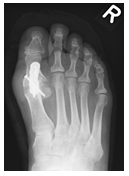

Durch die Fehlstellung der Großzehe (Hallux valgus) ist es zur Ausbildung einer Krallenzeh gekommen. Die Korrektur ist in manchen Fällen nur möglich, wenn beide Zehen begradigt werden. Im rechten Bild ist noch der Draht zu erkennen, der vier Wochen nach der Operation entfernt wird.

Der Fuß ist mit seinen knapp dreißig Gelenken und Muskeln eine komplexe anatomische Konstruktion, die im Alltag einer großen Belastung ausgesetzt ist. Eine Vielzahl von möglichen Fehlstellungen erfordert vom behandelnden Arzt große Erfahrung, um die Beschwerden beim Gehen, Stehen oder Sporttreiben der richtigen Ursache zuordnen zu können. Die häufigste Fehlstellung am Fuß ist der Zehenballen (Hallx valgus). Allein in Deutschland sind 10 Mio. Menschen betroffen, davon jeder Dritte bei über 65-Jährigen. Schmerzen vor allem an der Innenseite der Großzehe können das Gehen beschwerlich machen. Manchmal kommt es im Verlauf zur Verdrängung der daneben liegenden Zehe (Krallenzeh). Auch kann es durch Fehlbelastung zu Schmerzen unter der Fußsohle kommen.

Wenn die Beschwerden über einen längeren Zeitraum bestehen und durch angepasstes Schuhwerk nicht abklingen, kann eine operative Korrektur erfolgen. Ziel ist hierbei die Begradigung der Zehe(n), um die Belastbarkeit wieder herzustellen. Es gibt hierfür viele verschiedene operative Optionen mit unterschiedlichen Vor- und Nachteilen. Die Wahl des richtigen Operationsverfahrens erfordert vom behandelnden Arzt Fingerspitzengefühl und Erfahrung und ist für den langfristigen Verlauf entscheidend. Nachfolgend werden wesentliche Informationen hierzu aufgeführt.

Begradigung durch Knochenverschiebung

Hierbei wird der Mittelfußknochen nach außen verschoben und mit zwei kleinen Schräubchen wieder befestigt (Osteotomie nach Chevron). Ebenfalls wird ein verkürzter Muskel gelöst, damit der Zeh in gerader Position verbleibt (sog. laterales Release). Sollte die Fehlstellung auch innerhalb der Zehe vorliegen, wird auch ein kleiner Keil am Großzehengrundglied entnommen (Osteotomie nach Akin).